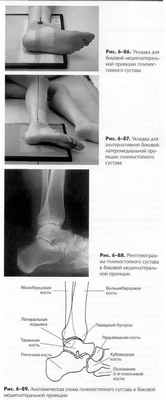

БОКОВАЯ ПРОЕКЦИЯ

- МЕДИОЛАТЕРАЛЬНАЯ ИЛИ ЛАТЕРОМЕДИАЛЬНАЯ: ГОЛЕНОСТОПНЫЙ СУСТАВ

Укладка пациента

Пациент лежит горизонтально, на боку, исследуемой стороной тела вниз (дайте пациенту подушку под голову), колено исследуемой ноги согнуто примерно на 45°, другая нога расположена снизу в качестве упора и фиксатора от ротации.

Укладка снимаемой области (медиолатеральная проекция)Щ

• Стопа должна быть направлена вдоль длинной оси снимка,

голеностопный сустав — в центре.

• По необходимости используйте подставку под колено ноги

ногу для ее фиксации в истинно боковой укладке.

• Стопа должна быть согнута в тыльном направлении так,

чтобы подошвенная плоскость составляла прямой угол с го

ленью. Сгибание следует выполнять без усилия, стараясь не

причинять неприятных ощущений пациенту.

Центральный луч

• ЦЛ идет перпендикулярно плоскости кассеты и направлен на

середину лодыжки.

• Минимальное РИП составляет 100 см.

Диафрагмирование.С четырех сторон максимально близко

к краям стопы, включая половину проксимальной области плюсны

и дистальную часть малоберцовой и большеберцовой костей.

Критерии оценки рентгенограммы Видимые анатомические структуры.• Дистальная треть большеберцовой и малоберцовой костей, при этом дистальный отдел малоберцовой кости наложен на дистальный отдел большеберцовой кости, таранная кость и пяточная кость в профиль, бугристость пятой плюсневой кости, ладьевидная кость и кубовидная кость.

Укладка.• Отсутствие ротации подтверждается наложением дистального отдела малоберцовой кости задней стороной большеберцовой кости. Большеберцово-таранный сустав будет равномерно открыт.

Диафрагмирование и ЦЛ.• ЦЛ и центр снимка должны находиться в середине голеностопного сустава. Область диафрагмирования должна включать примерно одну треть голени, пяточную кость, бугристость пятой плюсневой кости и окружающие мягкие ткани.

Параметры экспозиции.• Отсутствие движения во время экспозиции, а также оптимальные параметры экспозиции дают четкую визуализацию контуров костей и их трабекулярной структуры. Латеральная лодыжка должна быть видна через дистальный отдел малоберцовой кости и таранную кость. Должны быть различимы мягкие ткани для визуализации возможного выпота.

Альтернативная латеромедиальная проекция (рис. 6-87). Эта

проекция выполняется достаточно часто, хотя она более болезненна для пациента, но с ее помощью истинная боковая укладка достигается гораздо легче.